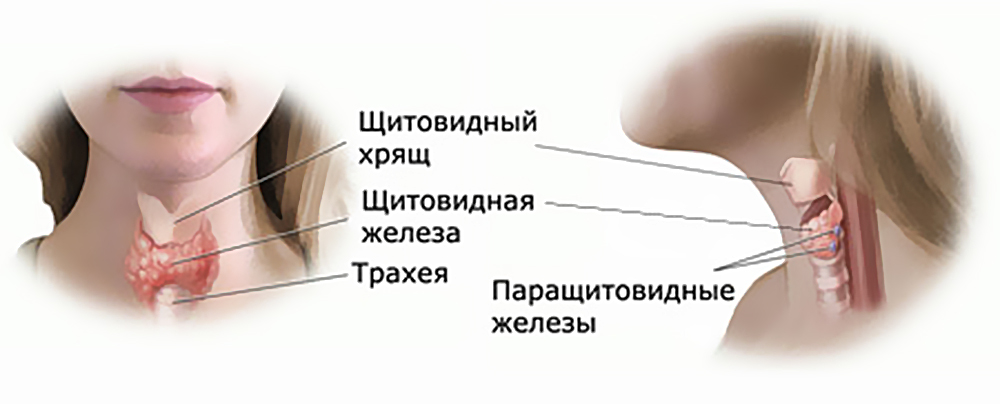

Иллюстрации и схемы по остеопорозу и паращитовидной железе